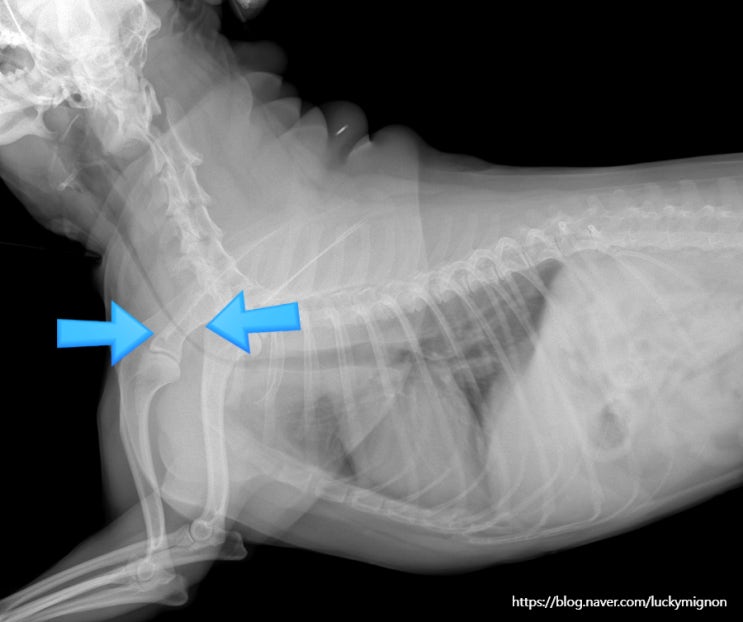

강아지 기관지협착 심장 초음파 지방종 수술 후기

안녕하세요! 8살이 넘어가면서 노견이 되어 가면서 스케일링이 필요하다 느껴 병원에 방문 했다 기관지협착...

폐고혈압 진단·치료 전략·증례 토론 글로벌 수의학 교육기관 V-ACADEMY가 오는 11월 10일(월)~11일...